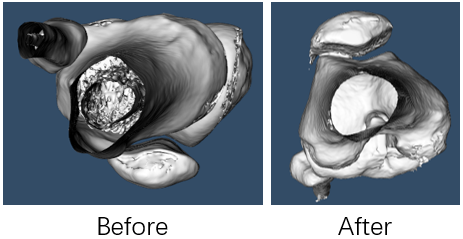

Cruciate ligament injury is very common in daily life. At present, many ligament reconstruction operations are based on the experience of doctors, and errors are inevitable. Extraction and reconstruction of cruciate ligament insertion is very important, which can help doctors to analyze and predict before surgery, and improve the success rate of surgery.